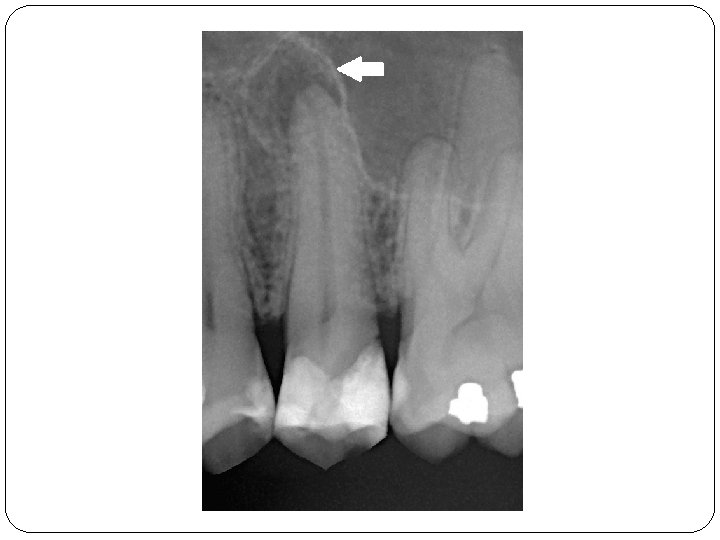

Wurzelbehandlung

Vor der Wurzelbehandlung Nach der Wurzelbehandlung